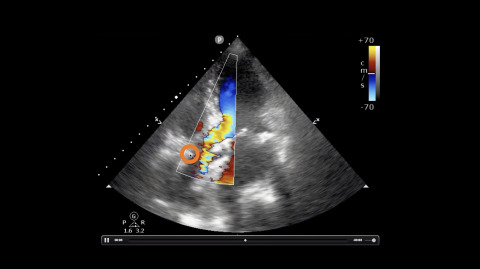

Aortic Insufficiency

Jacob Avila demonstrates the ultrasound findings of aortic insufficiency.

1 chapterApril 2020

Aortic Regurgitation Echo

1 chapterOctober 2019